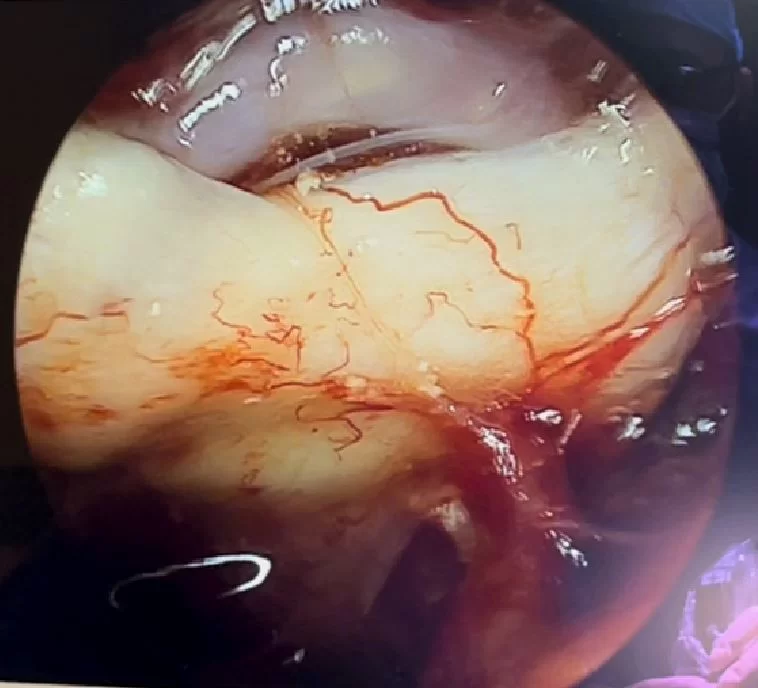

Η μαγνητική τομογραφία εγκεφάλου αναδεικνύει χωροκατακτητική εξεργασία (όγκο) στην περιοχή του εφιππίου, με σημαντική πίεση επί του οπτικού χιάσματος.

Αποφασίστηκε και διενεργήθηκε διαρρινική (δηλαδή μέσα από τη μύτη) ενδοσκοπική αφαίρεση του όγκου. Η αφαίρεση ήταν ολική.

Στη συγκεκριμένη ασθενή επιλέξαμε να αφαιρέσουμε τη βλάβη με τη βοήθεια του ενδοσκοπίου, μέσα από τη μύτη. Η ενδοσκοπική αφαίρεση επιτρέπει να ελεγχθεί πλήρως ολόκληρη η περιοχή του εφιππίου και να επιτευχθεί τελικά ολική αφαίρεση του όγκου χωρίς τομή στο κρανίο!